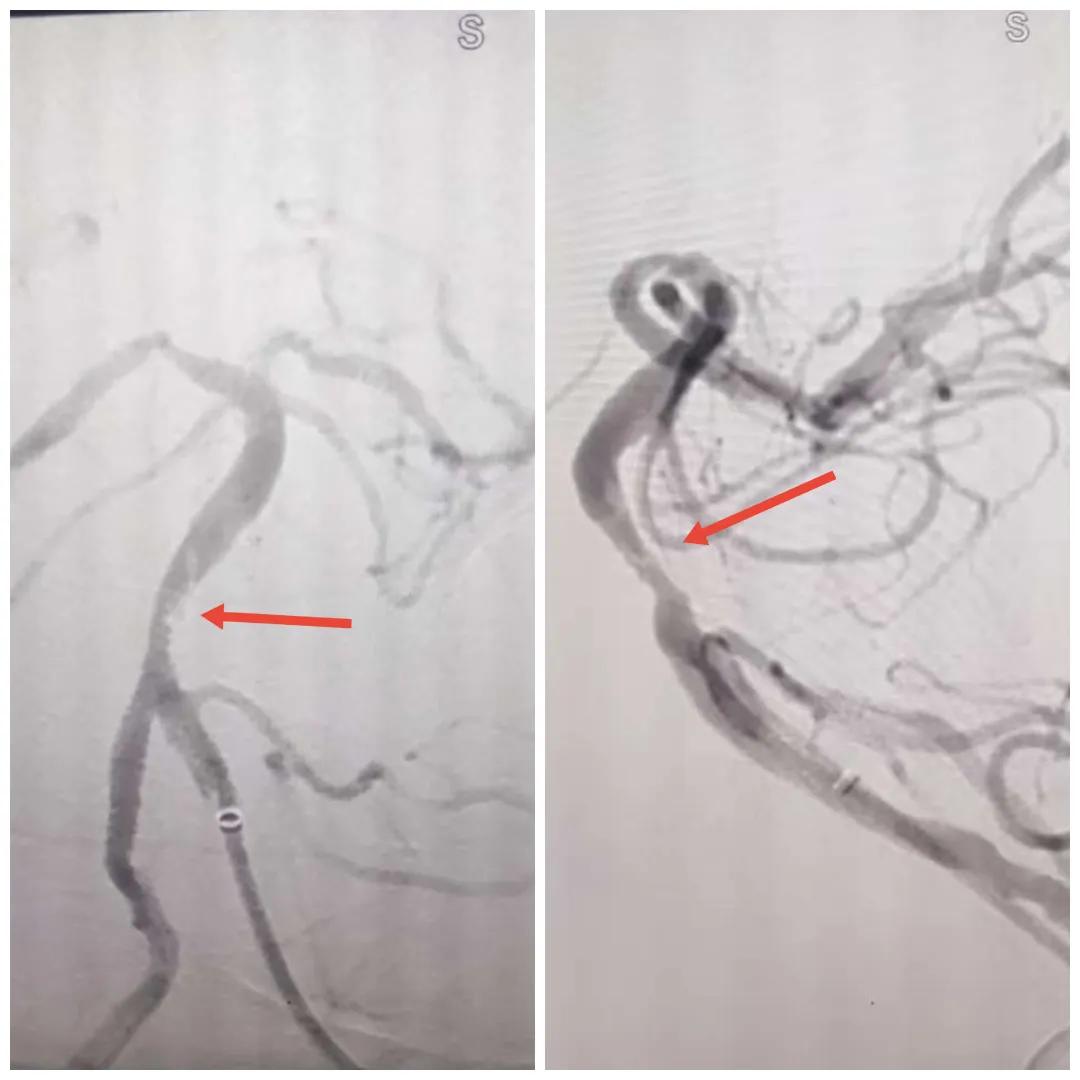

在經(jīng)造影后,主刀醫(yī)生腦一科副主任楊慶堂發(fā)現(xiàn)患者基底動脈下段重度狹窄且狹窄段以遠有大負荷血栓,其狹窄處考慮為動脈夾層,手術難度及風險較大。楊慶堂副主任在彭壯副主任醫(yī)師的協(xié)助下運用spaceman(太空人)技術,中間導管抵近血栓抽吸配合支架拉栓,成功開通血管。再次造影可見基底動脈管腔明顯增寬,遠端血管顯影良好,且等待20分鐘后造影仍顯示血流通暢。楊慶堂副主任考慮到本次手術時間不宜過長,現(xiàn)患者基底動脈及分支前向血流維持良好,給予其抗栓藥物應用后結束手術,并建議患者3個月后復查造影,明確其基底動脈夾層情況。

造影可見血管夾層和大量血栓形成

取栓后血管管腔增寬,前向血流良好